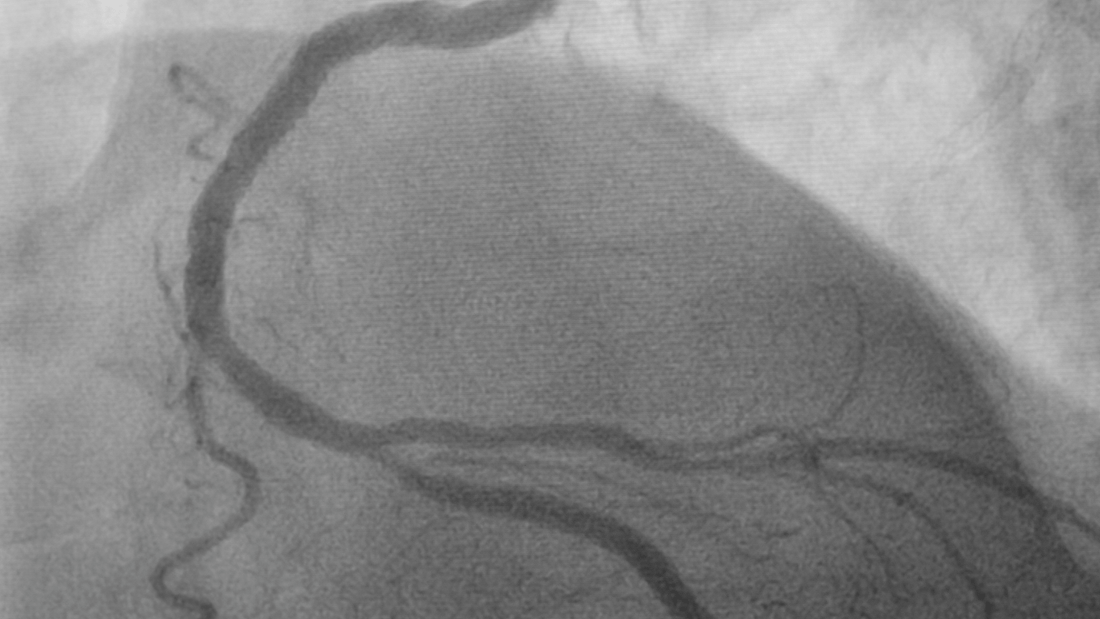

An angiogram, also known as coronary angiography, is a specialized medical imaging test that allows doctors to visualize how blood flows through the arteries of your heart.

It plays a critical role in identifying narrowing, blockages, or plaque buildup that may restrict blood flow and increase cardiovascular risk.

Unlike general heart tests such as an electrocardiogram (ECG) or stress test, an angiogram provides a direct, visual assessment of your coronary arteries. It helps physicians determine not only whether blockages are present, but also where they are located and how severe they might be. This makes the angiogram one of the most precise diagnostic tools for evaluating coronary artery disease.